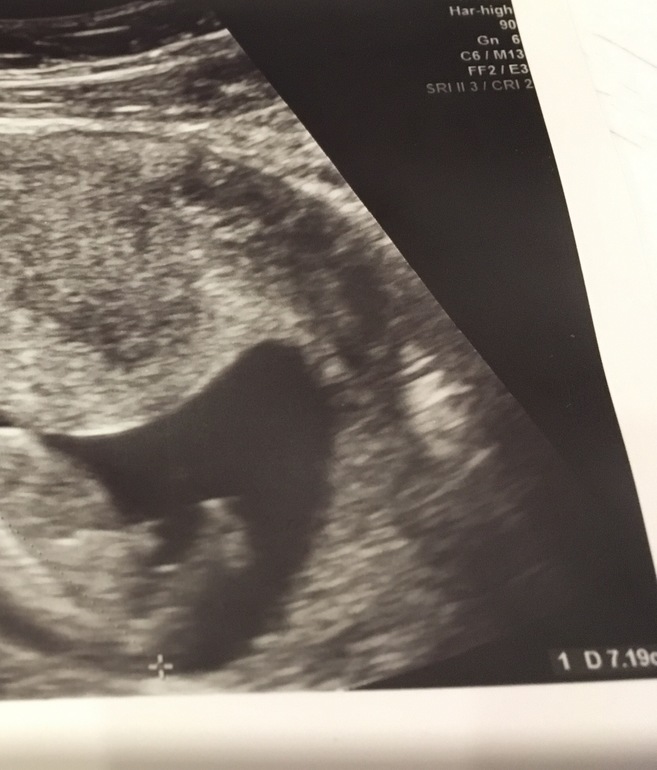

УЗИ, КТГ, доплерДевочки, это УЗИ на сроке 12,4 нед., по размерам 13,4 нед, на недельку опережаем. Узист сказал что ребенок на мальчика похож, а вы как думаете?)

У меня сейчас похожее очень в животе сидит:) точнее на таком же сроке был такой же половой бугорок. И мне кажется, что на девочку похоже:)))

Зависит от специалиста.Мне всех правильно говорил.Отличаются на вашем сроке они углом наклона только. У меня девочка похожа на ваше узи .

у моих мальчищек чсс на 1 скрининге было 172 и 174,так что это е показатель.Но вот пол мне оба раза правильно говорили уже на 1 скрининге.А по вашему фото не видно